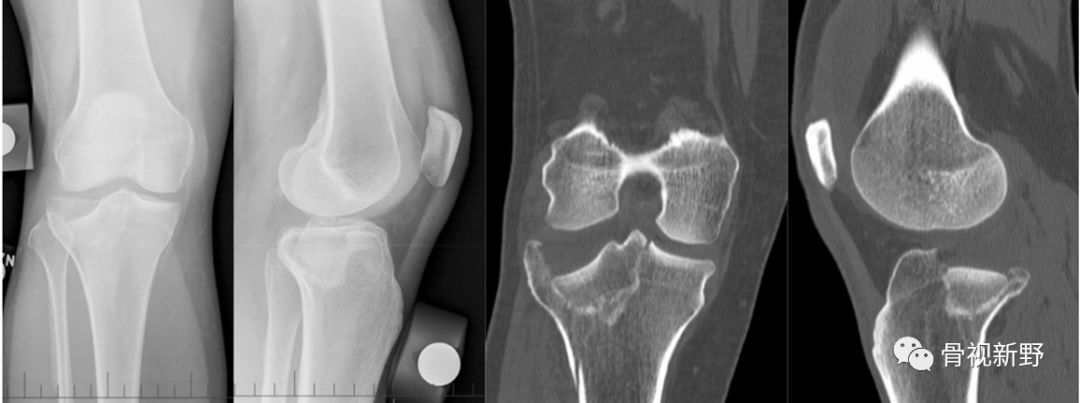

胫骨平台骨折占下肢骨折的5-8%[Weimann A 2013];占全身骨折的1%。其中部分类型(如Schatzker I-III型)的骨折、开放骨折或皮肤软组织条件差者;关节镜辅助手术者等,可经皮、微创螺钉固定。

胫骨平台骨折占下肢骨折的5-8%[Weimann A 2013];占全身骨折的1%。其中部分类型(如Schatzker I-III型)的骨折、开放骨折或皮肤软组织条件差者;关节镜辅助手术者等,可经皮、微创螺钉固定。本文对胫骨平台骨折常见的几种单纯螺钉固定理念、技术进行简要汇总。

51ys, F。胫骨外侧平台骨折(Schatzker II型)